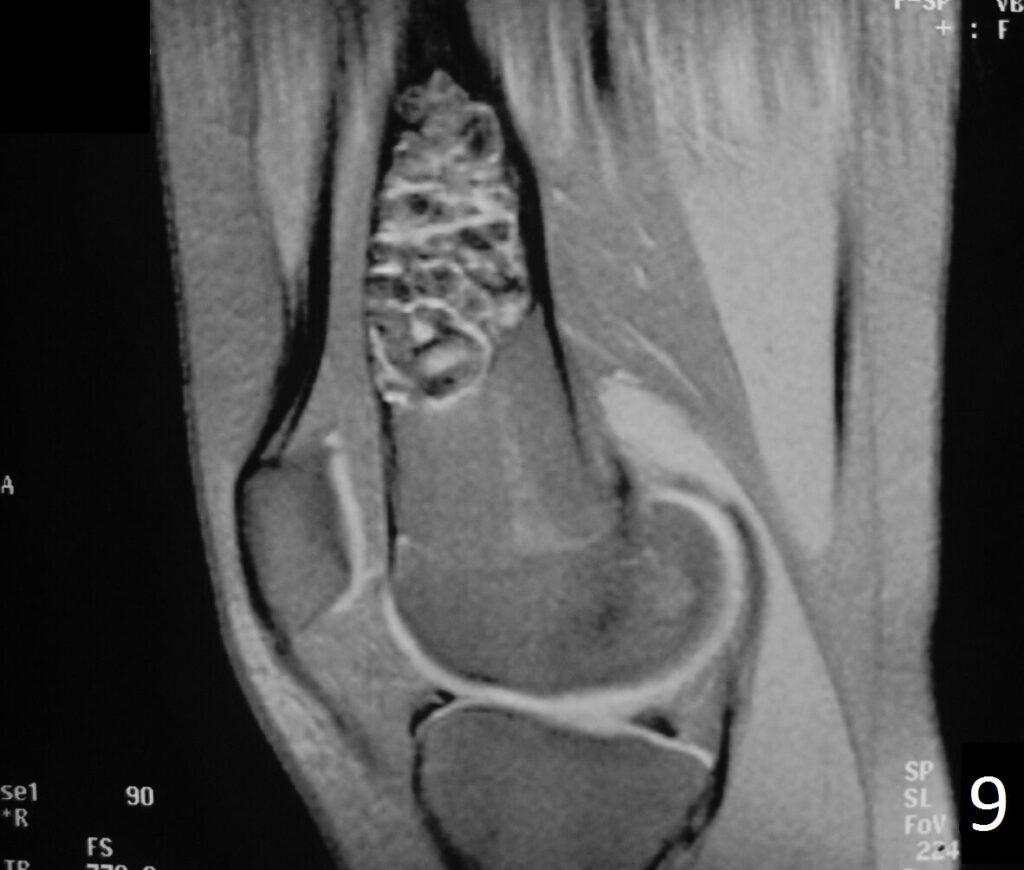

• Variable heterogeneneous signal on T2 (Fig. 9).

• Possible extensive hypercellular fibrous tissue and hemosiderin seen on T2

Fig. 6-9: Sagittal T1 (Fig. 6) and T2 (Fig. 7) MRI of the knee demonstrates a fibrous cortical defect. Axial T1W (Fig. 8) and T2W (Fig. 9) show a heterogeneous lesion on distal femur, compatible with nonossifying fibroma.